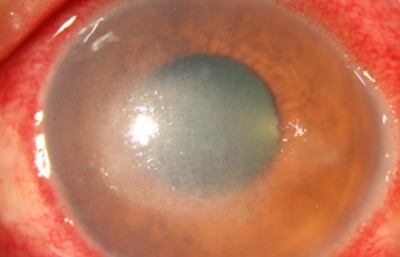

Superficie corneal irregular y grisácea, (Fig. 1, 2) con opácidades granulares en parche y formación de líneas epiteliales elevadas de aspecto granular (Fig. 3), que pueden arborizar dando imágenes de pseudodendritas. Opacidades superficiales satélites. (Figura 4) Inyección ciliar. Ulceración epitelial variante. (Figura 5).

Fig. 2 Síntomas de 25 días evolución